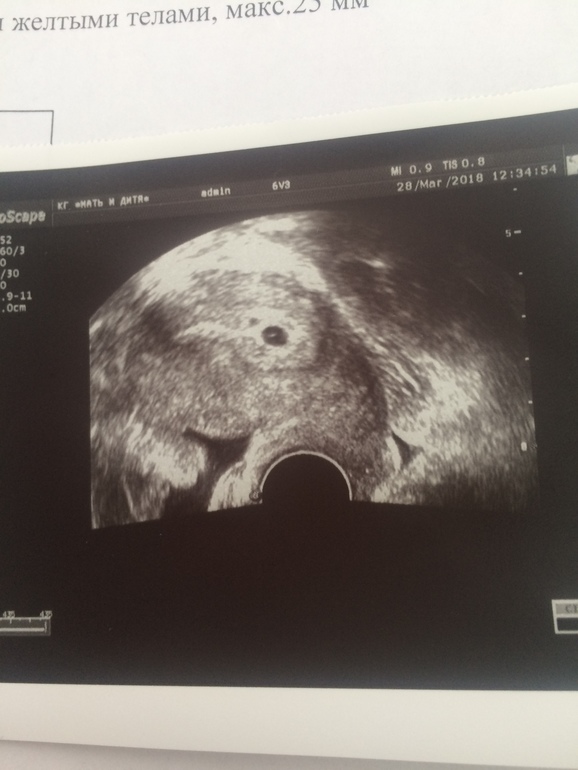

а узи обнаружили желтое

На узи обнаружили желтое 87 фото